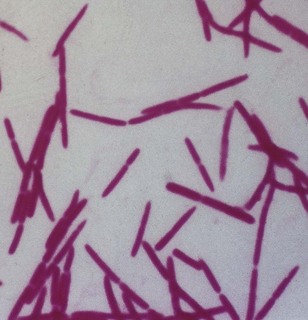

Gram-negative, strictly anaerobic, cigar-shaped bacilli with pointed ends (Fig. 18.1). Cells often have a central swelling. A Gram-stained smear of deep gingival debris obtained from a lesion of acute ulcerative gingivitis is a simple method of demonstrating the characteristic fusobacteria, together with spirochaetes and polymorphonuclear leukocytes (Fig. 18.2). These, together with the clinical picture, confirm a clinical diagnosis of acute ulcerative gingivitis.

Fig. 18.2 A Gram-stained smear obtained from deep gingival plaque of a patient with acute ulcerative gingivitis (see also Fig. 33.6) showing the fusospirochaetal complex. Note: the large cells are polymorphs.